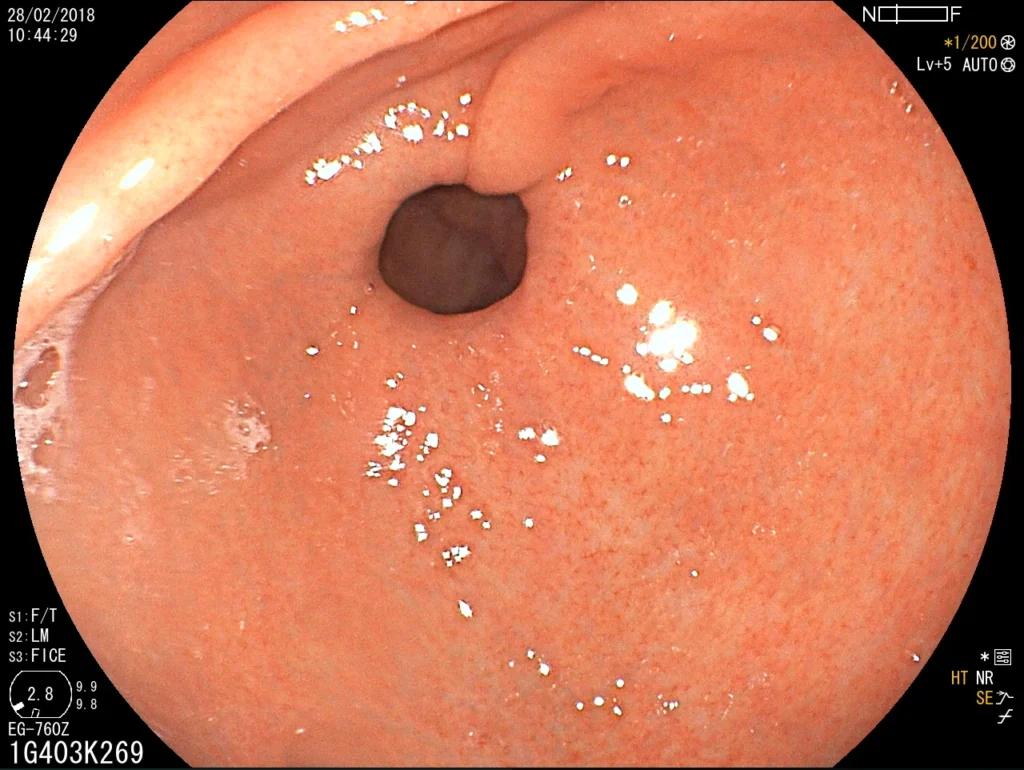

Introducción del gastroscopio bajo visión directa para examinar esófago, estómago y duodeno.